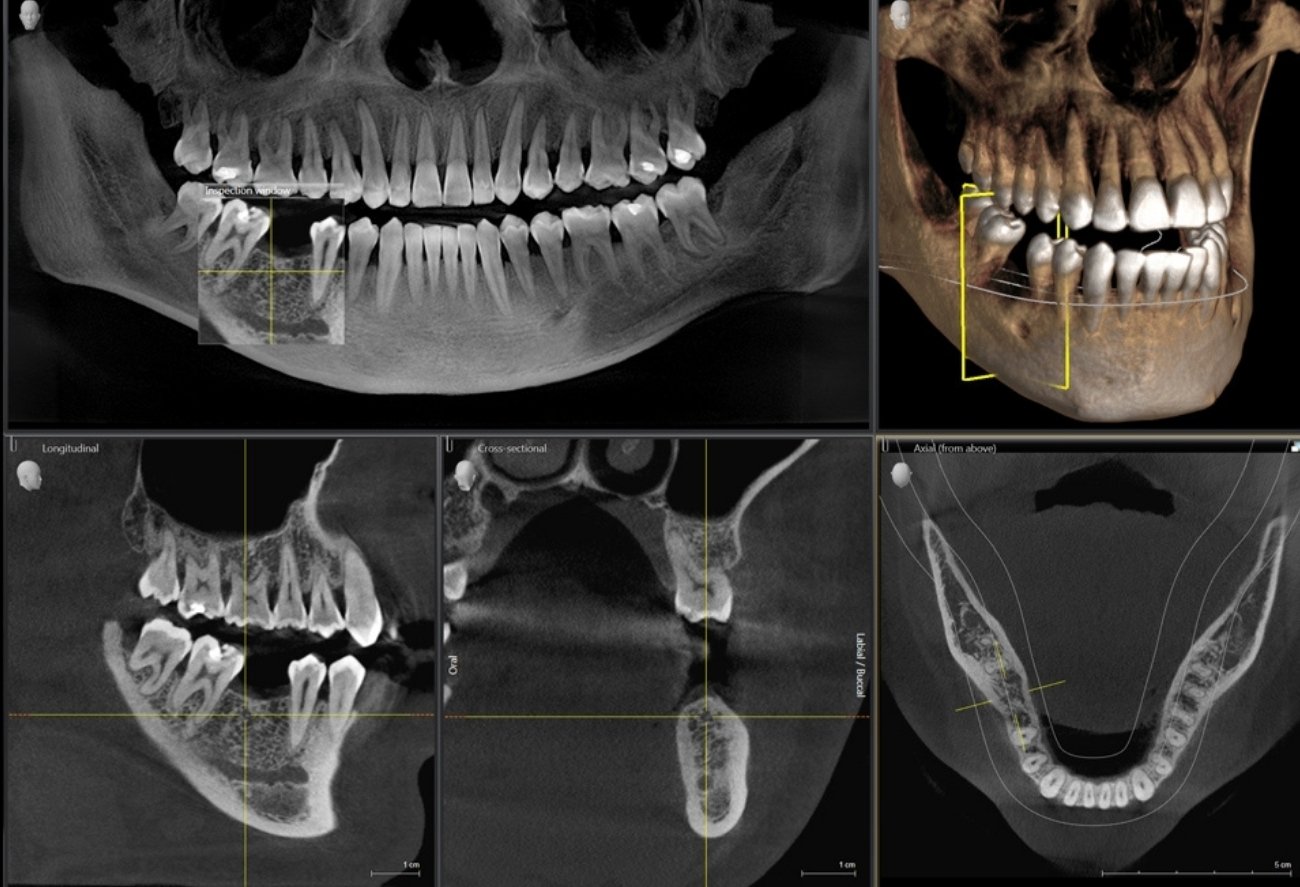

Приклади 3D-зображень: